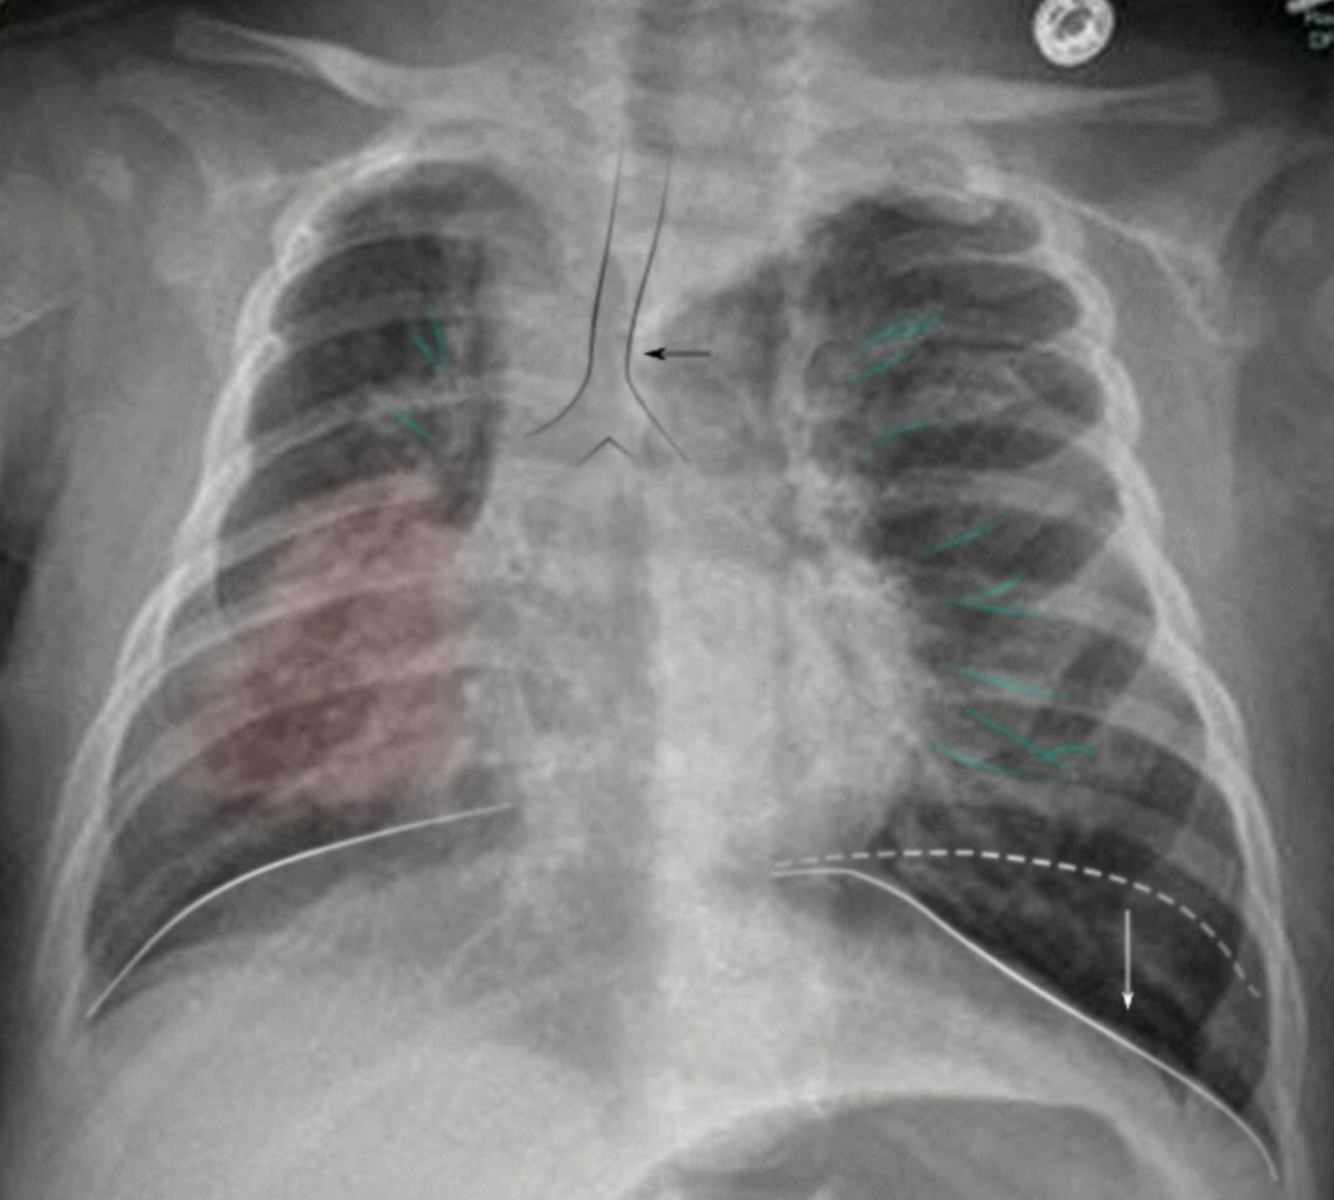

Atélectasie

++ à 72h postop

1. Clinique

2. Diag :

1. Gazo Aa

→ hypoxémie, ± PaCO2 faible et alcalose

2. Rx

1. collapsus lobaire → opacification homogène

2. Shift médiastinale coté ipsi

3. TTT

• Mobilisation précoce

• Manœuvres d’expansion pulmonaire → ⇡ pression+ en fin d’expiration

• Traitement de la condition sous-jacente

4. Prévention post chir → prescrivant opioïdes soulager la douleur → prudence car suppression de la toux